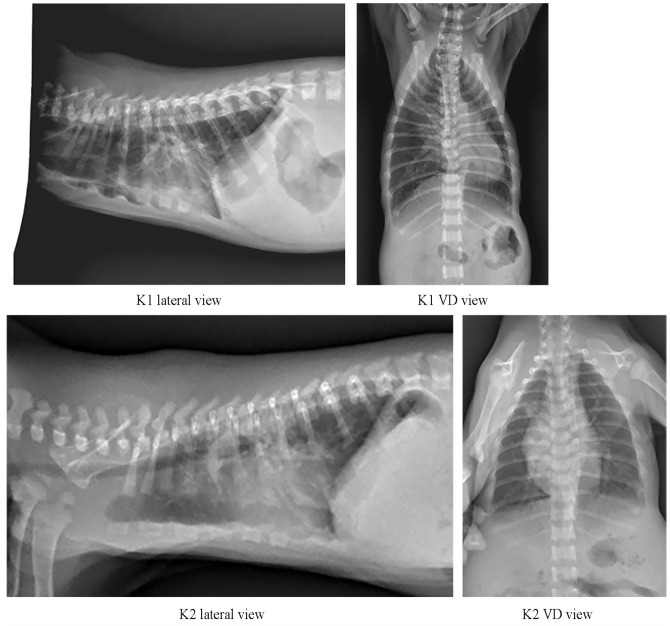

Case summary Two 18-day-old domestic shorthair kittens presented with dyspnoea, mild cyanosis, heart murmur, lung pattern, abnormal crawling and a marked dorsoventral flattening of the thorax. Deformity of the thoracic wall without pectus excavatum was diagnosed. Cardboard corsets tailored to each kitten were applied. This gave immediate respiratory relief, easing distress and pain. After 10 days, clinical and radiographic monitoring revealed normalisation of the shape of the chest wall with an improvement in general condition. At 6 months of age, clinical examination showed normal growth and development of both kittens, with a normal thoracic profile and shape also seen on radiographs. Relevance and novel information Data about flat-chested kitten syndrome and its aetiopathogenesis, treatment and outcome are scarce, but there is significant experience among breeders that is shared through online communities. High mortality rates are reported. The use of a cardboard splint appears to be novel in the published literature; in this case report, it proved to be a rapid and easy solution. For this reason, cardboard splints could be considered as a first approach for the clinical management of flat-chested kitten syndrome.